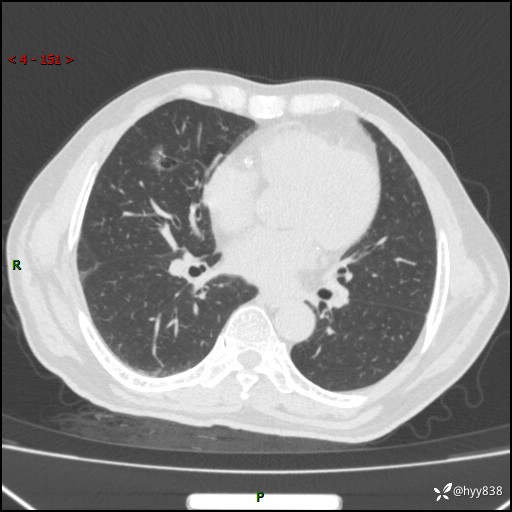

现病史:患者4月前无明显诱因后背正中间疼痛,间断阵痛,无低热、咳嗽,盗汗、咯血、胸痛、喘气等不适,2024-2-25当地市第二人民医院胸部CT提示“1.双肺感染病变;2.右肺中叶结节灶;3.双肺肺气肿并肺大泡4.主动脉及冠脉硬化,今为求明显结节性质遂来我院门诊就诊,门诊以“肺占位”收治入院。 起病以来,患者精神饮食睡眠一般,大小便正常,体力体重无明细变化。

胸部CT平扫(2024.2)